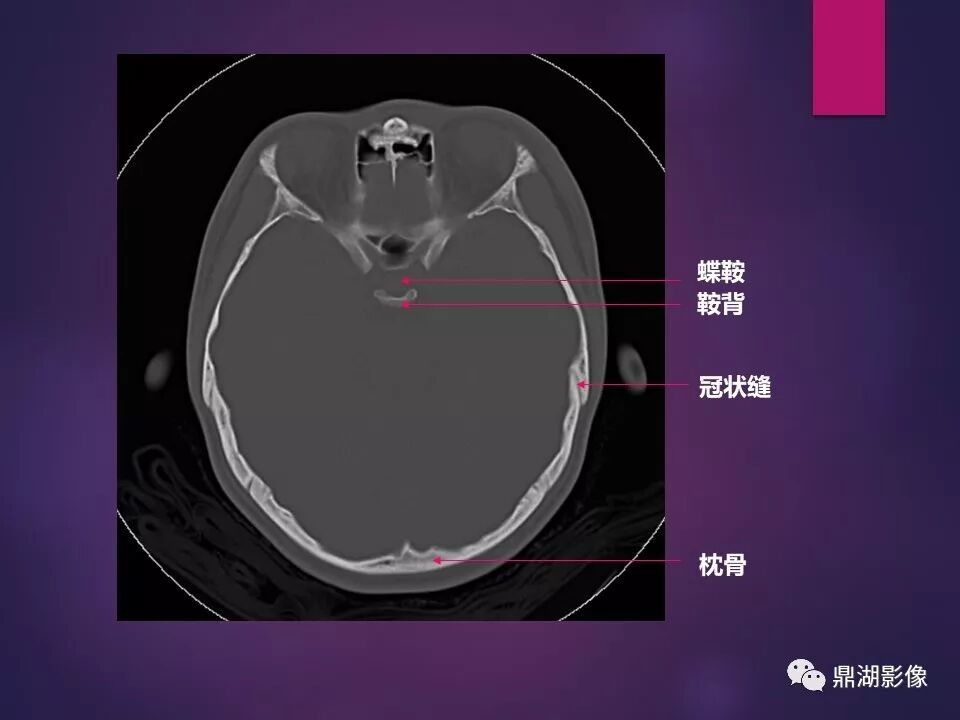

来源于:鼎湖影像 贵阳医学院医学影像系